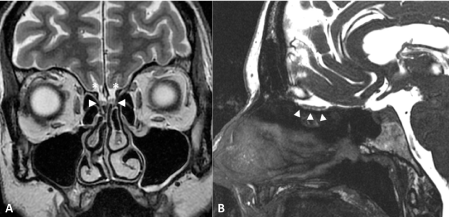

Figure 2: Patient 10 with Isolated Congenital Anosmia.

MRI of aplastic olfactory bulbs on coronal T2-weighted imaging (A) and sagittal Fast Imaging Employing Steady-state Acquisition, FIESTA (B). The olfactory fossae (arrowheads) does not contain any olfactory bulb. Right olfactory fossa contains a small artery. Olfactory sulci are not visualized. View Figure 2